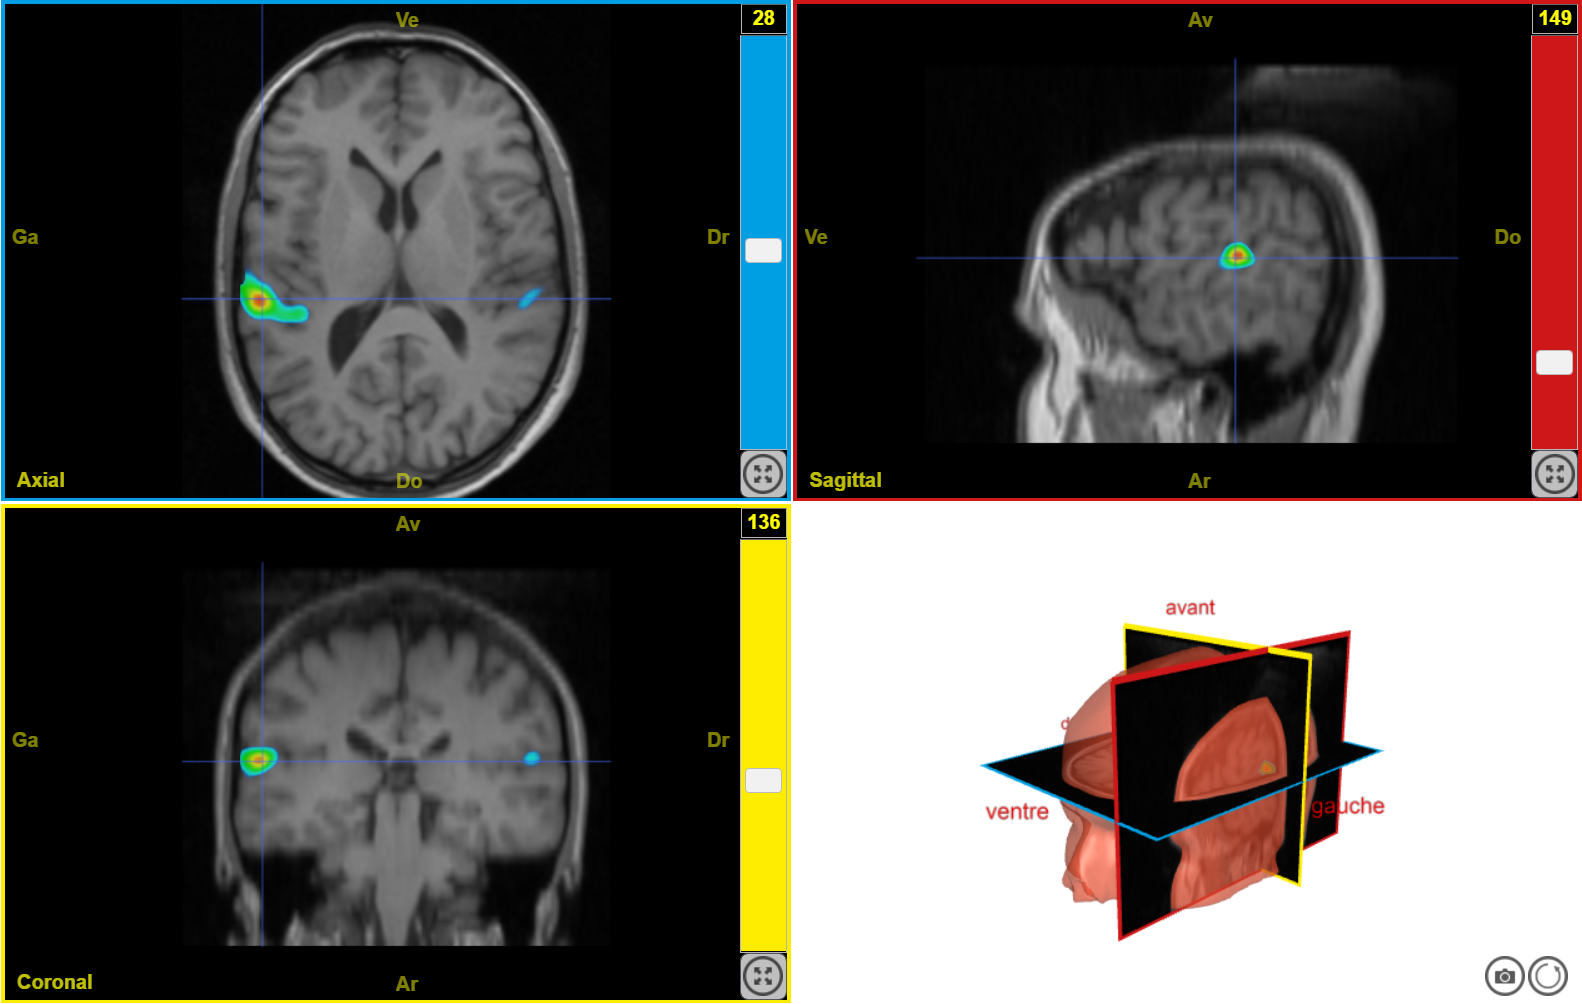

IRMf syllabes seuil 70